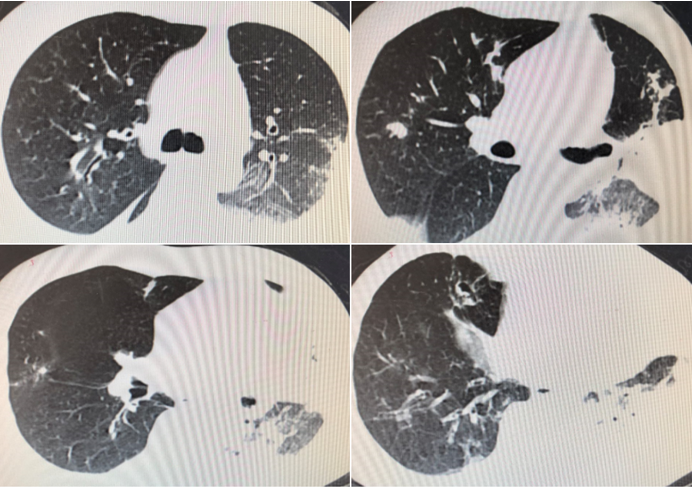

胸部CT(3月28日)(图7)。